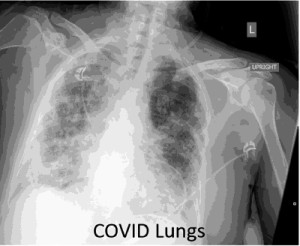

Tens of thousands of coronavirus survivors have been left with irreversible lung damage after contracting the illness doctors have warned.

Tens of thousands of people will need to be recalled to hospital after a serious covid 19 infection to check if they have been left with permanent lung damage doctors have told the bbc. But covid 19 appears to often affect both lungs. Doctors are still studying whether these effects are permanent or might heal over time.

While the majority of covid 19 deaths have occurred in people who are older. After a serious case of covid 19 a patients lungs can recover but not overnight. That scarring stiffens the lungs making it hard to get enough oxygen.

Additionally covid 19 scarring rates may end up being higher than sars and mers patients because those illnesses often attacked only one lung.